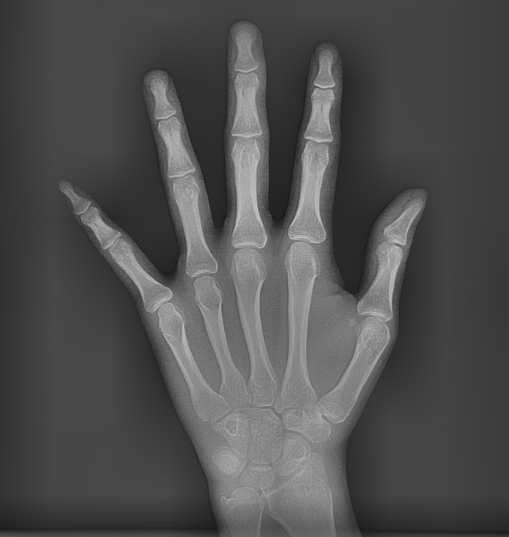

상일동 어린이 교정 상담을 위해 내원하시면

손 x ray를 찍는 이유도

성장이 얼마나 남았는지를 체크하기 위해서입니다!

250120 성장판이 안닫혔으면 턱 성장을 유도해볼 수 있는거죠~~